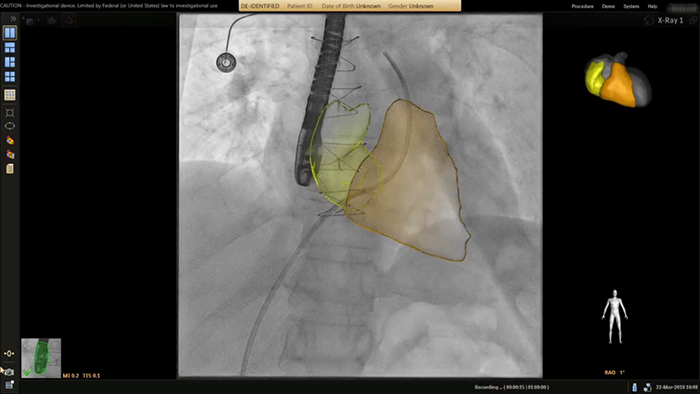

Guía en tiempo real de SmartCT

La herramienta de aplicación clínica para terapia guiada por imagen SmartCT de Philips permite a cualquier usuario clínico adquirir imágenes 3D, independientemente de su nivel de experiencia con la adquisición de imágenes 3D*. Mediante la pantalla táctil en la mesa, puede acceder a protocolos de adquisición 3D clínicamente personalizados y a herramientas avanzadas de visualización y medición que representan el tipo y la extensión de la enfermedad con gran detalle. *El nivel de experiencia necesario del usuario se especifica en las instrucciones de uso como el perfil del usuario previsto.